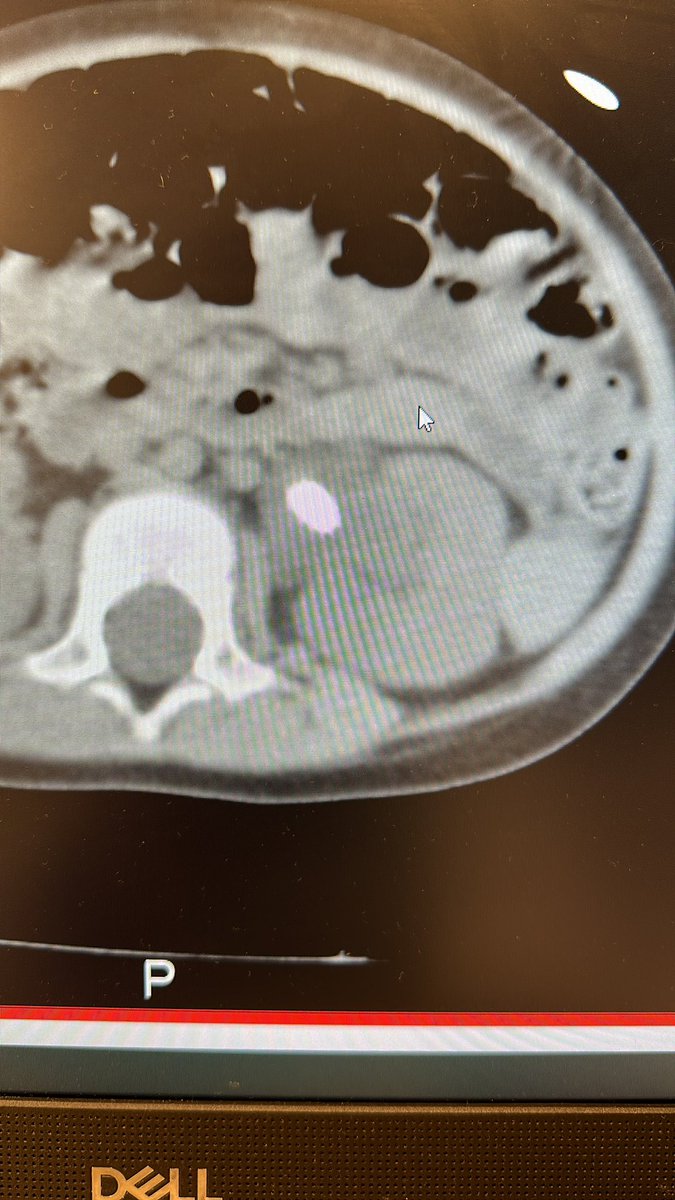

Paciente de 3 años, litiasis renal de 18x14x13 mm y litiasis ureteral.

#lupeyenchile #pedsendourology #endouroinfantil #endourologia #drreed (@pirricu)